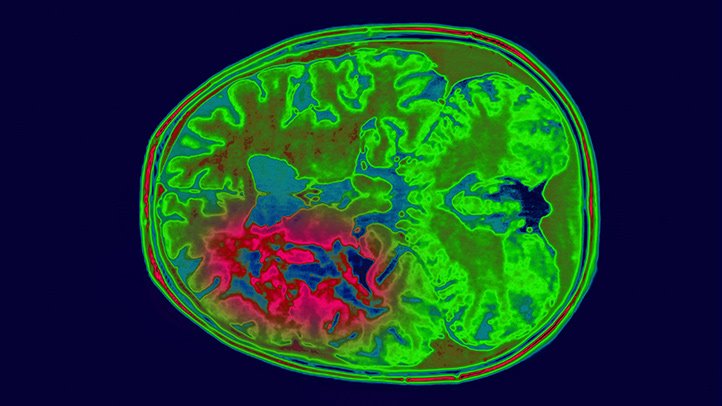

De tydligaste varningssignalerna gäller misstänkta samband mellan mobiltelefoner och elakartade hjärntumörer (glioblastom), prostatacancer, manlig och kvinnlig infertilitet och sköldkörtelcancer.

Ny statistik från socialstyrelsen visar att antalet diagnostiserade fall av hjärntumörer i öppen vård ökar kraftigt. 2017 behandlades sammanlagt 8 917 patienter i öppenvården för malign eller benign tumör i hjärnan eller i centrala nervsystemets hinnor, eller för tumör av okänd natur i hjärnan. Det är en ökning med 167 procent sedan 2001.

Den största patientgruppen är de som fått en elakartad hjärntumör. Jämfört med år 2001 har den gruppen ökat med 114 procent, från 1 340 patienter år 2001.

”Eftersom den vanligaste undergruppen av malign hjärntumör i allmänhet uppges vara maligna tumörer av grad IV (kallas också glioblastom eller glioblastoma multiforme) som är förenad med kort överlevnad, är det uppseendeväckande och illavarslande att denna patientgrupp, malign tumör i hjärnan, ökat kontinuerligt under den senaste tioårsperioden” skriver journalisten Mona Nilsson i Newsvoice.

I maj förra året exploderade en bomb i England. Då släpptes en vetenskaplig rapport som visade en fördubbling av antalet fall av den mest aggressiva och dödliga formen av hjärntumör, glioblastom, från 1995 till 2015 – under samma period som mobiltelefonanvändningen ökade från 15 procent till 95 procent.

Antalet fall som ingick i studien var 81 135. Antalet fall av glioblastom ökade från 983 år 1995 till 2 531 år 2015. Ökningen var statistiskt signifikant i alla åldersgrupper. Den största ökningen fanns hos personer äldre än 55 år. Den genomsnittliga överlevnadstiden för glioblastom efter diagnos är bara ett år.

Det anmärkningsvärda i den engelska forskarrapporten var inte bara fördubblingen av antalet fall, utan också att den största ökningen av tumörer var lokaliserad till det område i huvudet som mobiltelefonanvändare brukar hålla sin mobiltelefon tryckt mot, vid örat och hjärnans pannlob och tinninglob.